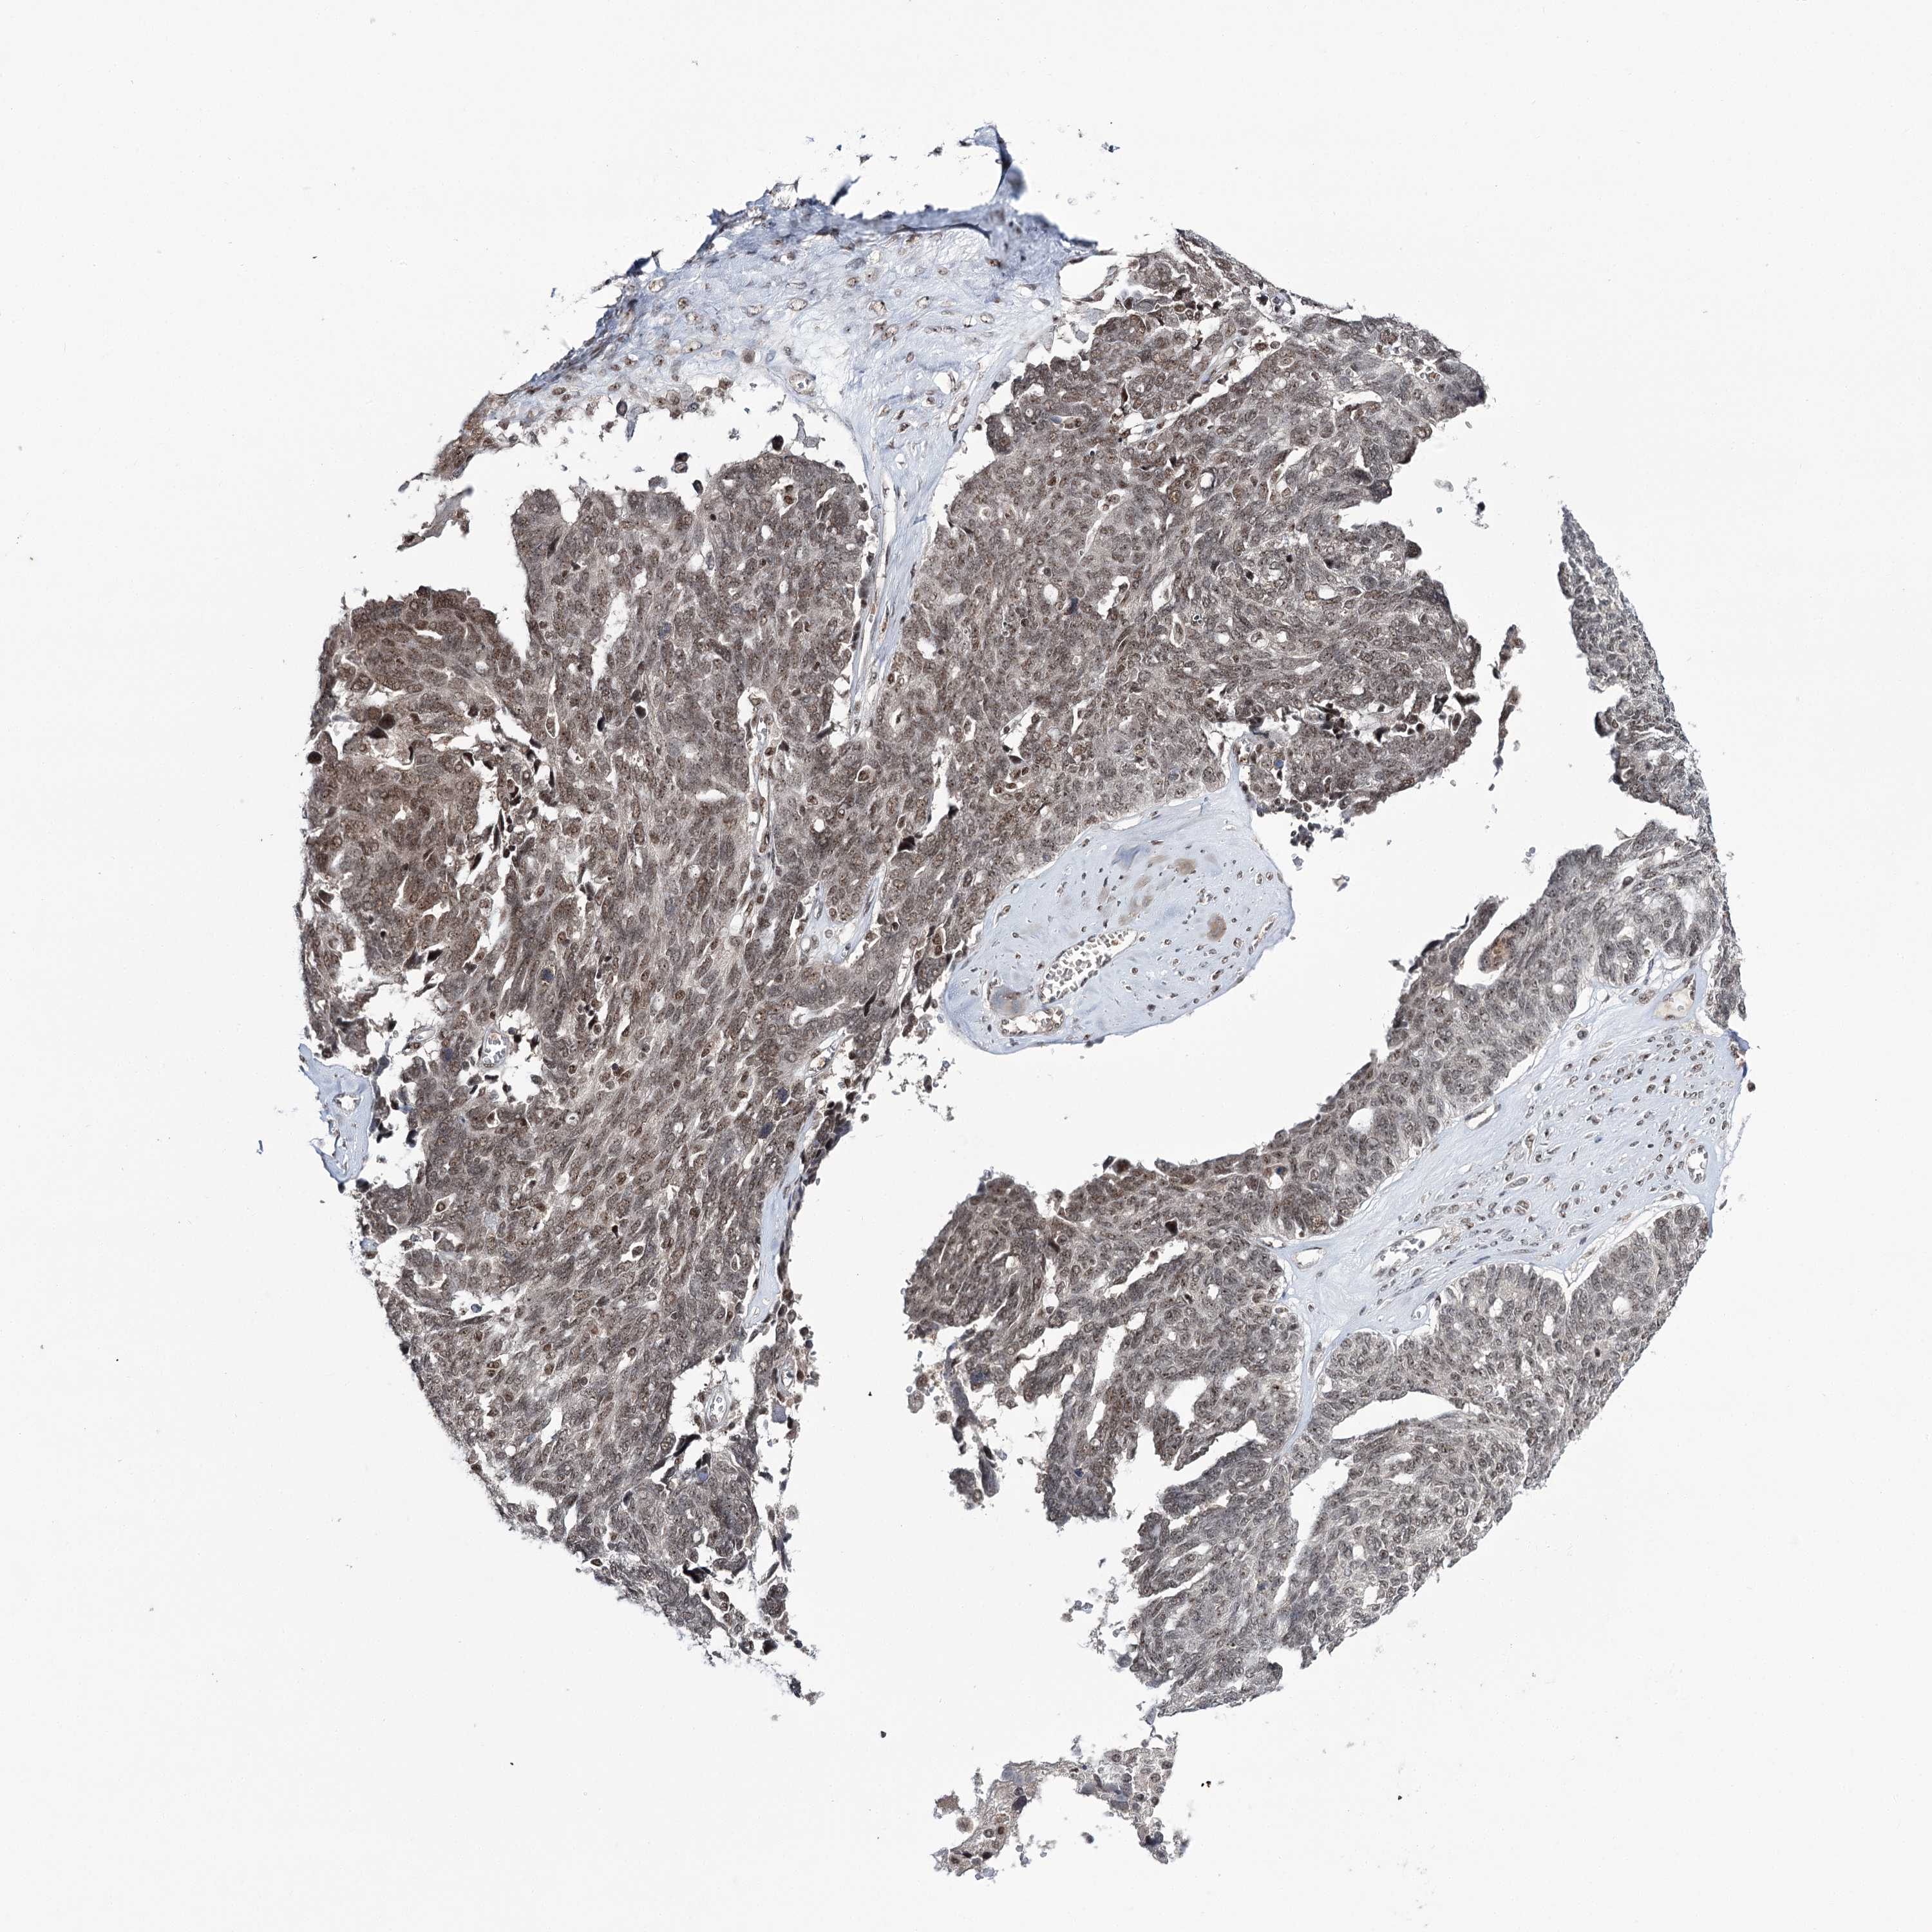

OVARIAN CANCER - Protein expressioni

A mouse-over function shows sample information and annotation data. Click on an image to view it in a full screen mode. Samples can be filtered based on level of antibody staining by selecting one or several of the following categories: high, medium, low and not detected. The assay and annotation is described here.

Note that samples used for immunohistochemistry by the Human Protein Atlas do not correspond to samples in the TCGA dataset.

Antibody stainingi

Antibody staining in the annotated cell types in the current human tissue is reported as not detected, low, medium, or high, based on conventional immunohistochemistry profiling in selected tissues. This score is based on the combination of the staining intensity and fraction of stained cells.

Each image is clickable and will lead to virtual microscopy that enables deeper exploration of all samples and also displays staining intensity scores, fraction scores and subcellular localization as well as patient and tissue information for each sample.

Antibody CAB037153

Staining

High

Medium

Low

Not detected

Intensity

Strong

Moderate

Weak

Negative

Quantity

>75%

75%-25%

<25%

None

Location

Nuclear

Cytoplasmic/membranous

Cytoplasmic/membranous,nuclear

Cystadenocarcinoma, serous, NOS

Carcinoma, endometroid

Cystadenocarcinoma, mucinous, NOS

Carcinoma, NOS